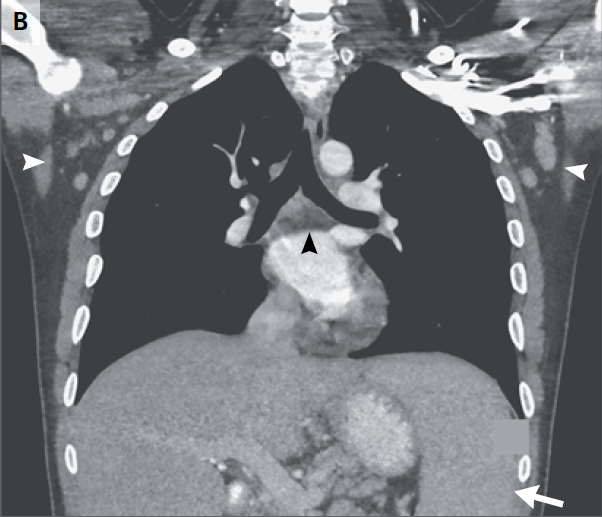

RMN de cráneo mostró tejido blando anormal a lo largo de las paredes anterior y lateral del seno esfenoidal izquierdo, en el vértice de la órbita izquierda extendiéndose posteriormente en el seno cavernoso izquierdo. Este tejido blando era de densidad intermedia tanto en una imagen potenciada en T2 (Figura A) Y una imagen potenciada en T1 con contraste (Figura 1B). Una imagen de RMN con contraste, coronal (Figura 1C) mostró aumento anormal en la unión del seno cavernoso y la cavum de Meckel en el lado izquierdo, con realce de tejido que se extendía a la parte interna del foramen oval.

Figura 1

Estudios por imágenes de los senos paranasales y órbitas.

RMN DE ÓRBITAS REALIZADA EN OTRO HOSPITAL. Una imagen en T2 (Panel A)y una T1 con contraste (Panel B) muestra tejido de densidad intermedia tapizando el seno esfenoidal y afectando el vértice de la órbita izquierda y el seno cavernoso (flechas). Un corte coronal en T1 (Panel C) muestra realce de partes blandas extendiéndose inferiormente al foramen oval. Una TC de órbita (Panel D) muestra que el hueso entre el seno esfenoidal y el vértice de la órbita están relativamente intactos a pesar de la presencia de tejido con densidad de partes blandas anormal a ambos lados (flecha).

TC de las órbitas (Figura 1D) reveló que el hueso entre el tejido blando anormal en el seno esfenoidal izquierdo y el tejido blando anormal en el vértice de la órbita izquierda estaba prácticamente intacto.